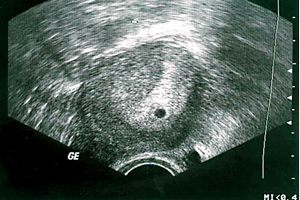

Не дивлячись на те, що всередині вже відбуваються значні зміни, тест на виявлення наявності нового життя всередині матері і раніше може бути негативним - і це нормально. Адже у вас ще навіть немає затримки. У крові матері вже досить високий рівень хоріонічного гонадотропіну, який в нормі дуже швидко наростає. І хоча тести, призначені для домашнього використання поки ще не працюють, на цьому терміні можлива діагностика при допомогою аналізу крові на ХГЧ. На такому терміні УЗД показує лише наявність жовтого тіла, яке замість того, щоб зменшуватися, буде збільшуватися в розмірах. Його завдання виробляти прогестерон - гормон, який зберігає вагітність.